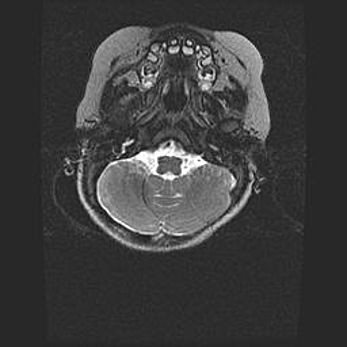

Мальформация Денди-Уокера. Киста задней черепной ямки.

Агенезия мозолистого тела.

Возраст: 2,5 месяца

Вес: 2420 г

Пол: женский

Окружность головы: 37 см

Срок гестации: 32 недели

Мальформация Денди—Уокера — редкий вид патологии ЦНС, представляющий собой врожденный порок развития каудального отдела ствола и червя мозжечка, ведущий к неполному раскрытию срединной (Мажанди) и латеральных (Лушка) апертур IV желудочка мозга. Для этогно синдрома характерна триада симптомов: гипотрофия червя мозжечка и/или полушарий мозжечка, кисты задней черепной ямки, гидроцефалия различной степени. В 70% случаев порок сочетается и с другими аномалиями головного мозга, в частности с агенезией мозолистого тела.